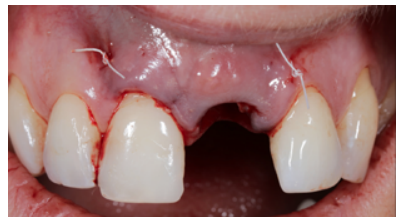

Clinical case: A 32-year-old female patient who attended for a possible root fracture of the upper left central incisor (ULCI), accompanied by a periodontal abscess at the bottom of the vestibule of the same tooth. A clinical and radiological examination established that the prognosis of the ULCI was unfavourable for conservative treatment. After evaluating the clinical features of the case, the treatment plan to extract the ULCI followed immediately by an osseointegrated implant (OII) and loading of a provisional prosthesis on the implant.

The physiological processes that take place after the extraction of a tooth are drastic, as they entail a series of modifications in the soft and hard tissues of the alveolar complex. Mainly, the microvascularisation of the architecture that surrounds the tooth suffers damage and atrophy that culminates in a decrease in the vascular supply provided by the periodontal ligament1-4. This results in a series of resorption processes discussed in this description of a clinical case.